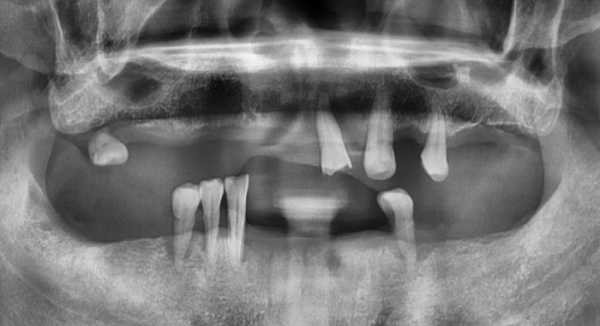

임플란트 전후사진